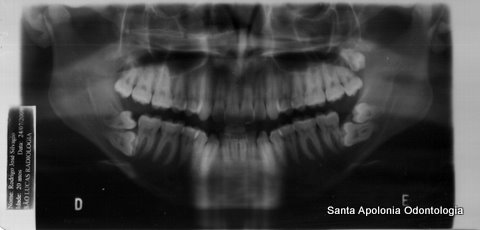

Rx Panoramica necessária antes da Cirurgia do Terceiro Molar, aqui mostra 7 dentes do Siso

Radiografia Panorâmica mostra a situação dos dentes do siso